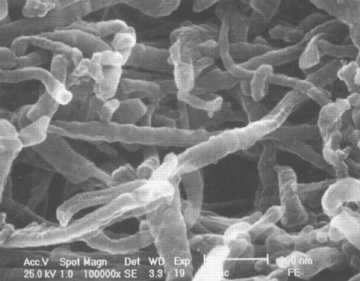

Fig. 1: Dentina mineralizada

El 90% del contenido orgánico del tejido dentinario es COLÁGENO, una glucoproteína fibrosa, insoluble con gran resistencia a la tracción; integra junto con proteoglicanos y otras glicoproteínas la matriz orgánica dentinaria (Figura 2).